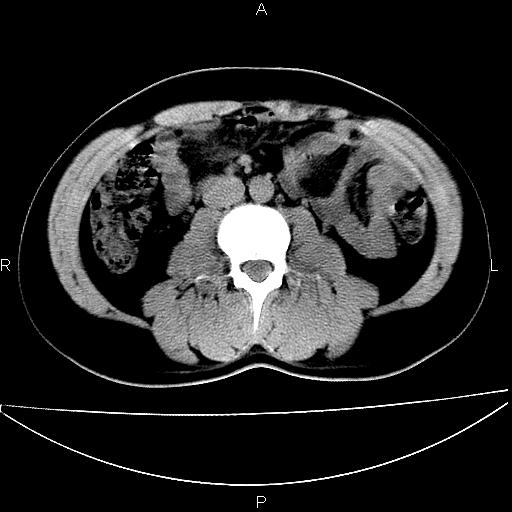

男 25岁 自述 尿频尿急,排尿困难20多天.无腰痛, b超说左肾盂轻度积水,左输尿管上端扩张.未见结石影. ct我看双侧肾盂轻度积水,双输尿管上端都扩张,大家看看能看见结石吗?

双肾轻度积水,双侧输尿管上段扩张(原因待查)。

双输尿管扩张下端未见高密度结石和输尿管晕轮征,不好说是结石.增强后如何?

双肾轻度积水,未见明确结石,薄层对结石检出率较高。

双肾盂及双输尿上段轻度积水,双输尿管未见明显结石影。